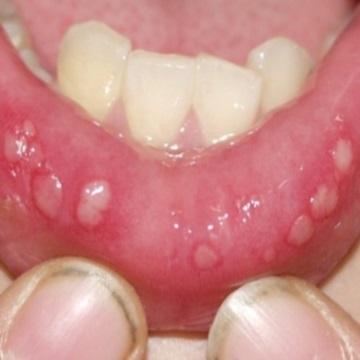

1. 아프타성 구내염

가장 많은 수를 차지하고 있습니다. 궤양성이라 부르기도 하는데 하얗거나 노르스름한 막으로 덮힌 염증이며 이 주변은 빨간 테두리가 보입니다. 뺨 안쪽, 혀, 잇몸, 입술 안쪽에 생기기 쉽고 1~2주 정도면 자연스럽게 개선되는 경향이 많습니다.

음식을 섭취하거나 음료를 마시면 쓰리면서 아린 증상이 나타납니다. 원인은 면역력 저하, 과로, 영양부족, 수면부족, 스트레스, 호르몬 불균형, 생리전, 임신 등으로 볼 수 있는데 면역력이 떨어져 있을 때 걸리기 쉽습니다.